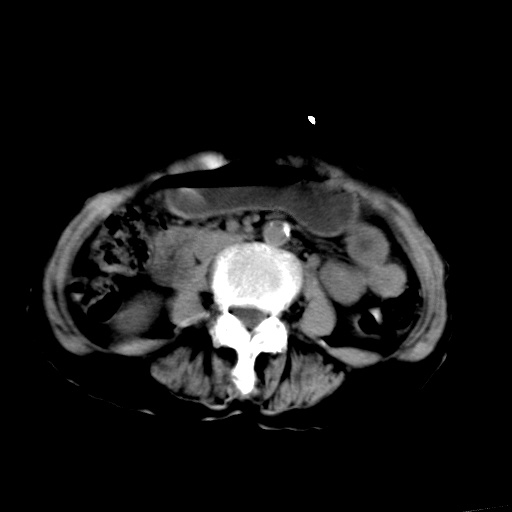

以下是引用杀毒软件在2009-3-4 17:38:00的发言:[br]为何没有喝照影剂呀? 胆总管及肝内胆管扩张,增强吧。[br][br]考虑-----十二指肠占位----建议----十二指肠镜检查[br][br]

以下是引用jiangjing在2009-3-4 17:45:00的发言:[br]低位胆道梗阻。十二指肠降段局部管壁增厚。扫描效果不理想,建议ct增强及ercp。

以下是引用杀毒软件在2009-3-4 17:38:00的发言:[br]为何没有喝照影剂呀? 胆总管及肝内胆管扩张,。增强吧。[br][br]考虑-----十二指肠占位----建议----十二指肠镜检查[br][br][br][br][本贴已被 杀毒软件 于 2009-3-4 17:56:38 修改过]